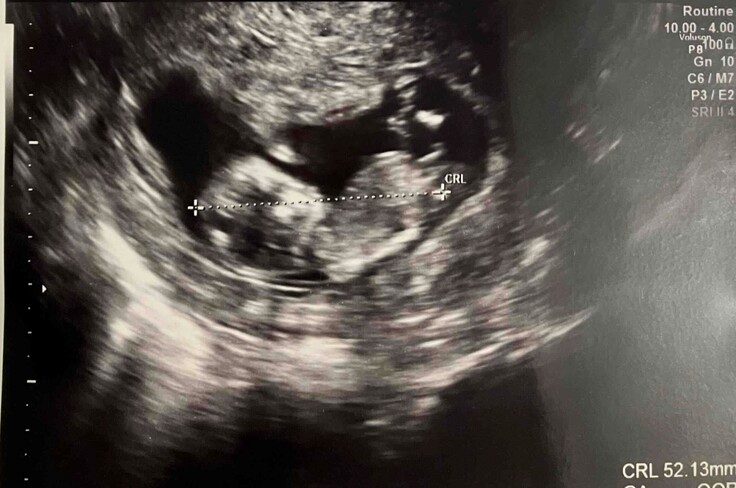

新しい命を授かりました。

お陰様で顕微鏡受精を受けることができ、妊娠までたどり着くことができました。READYFORを通じてサポートいただきました皆様、本当にありがとうございました。

今は安定期に入り、夫婦ともにようやく安堵と喜びをかみしめながら、この小さな命を大切に育んでおります。